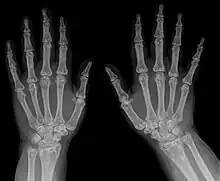

Diagnostic methodX-ray, ultrasound[3]

Osteopoikilosis

• X-ray